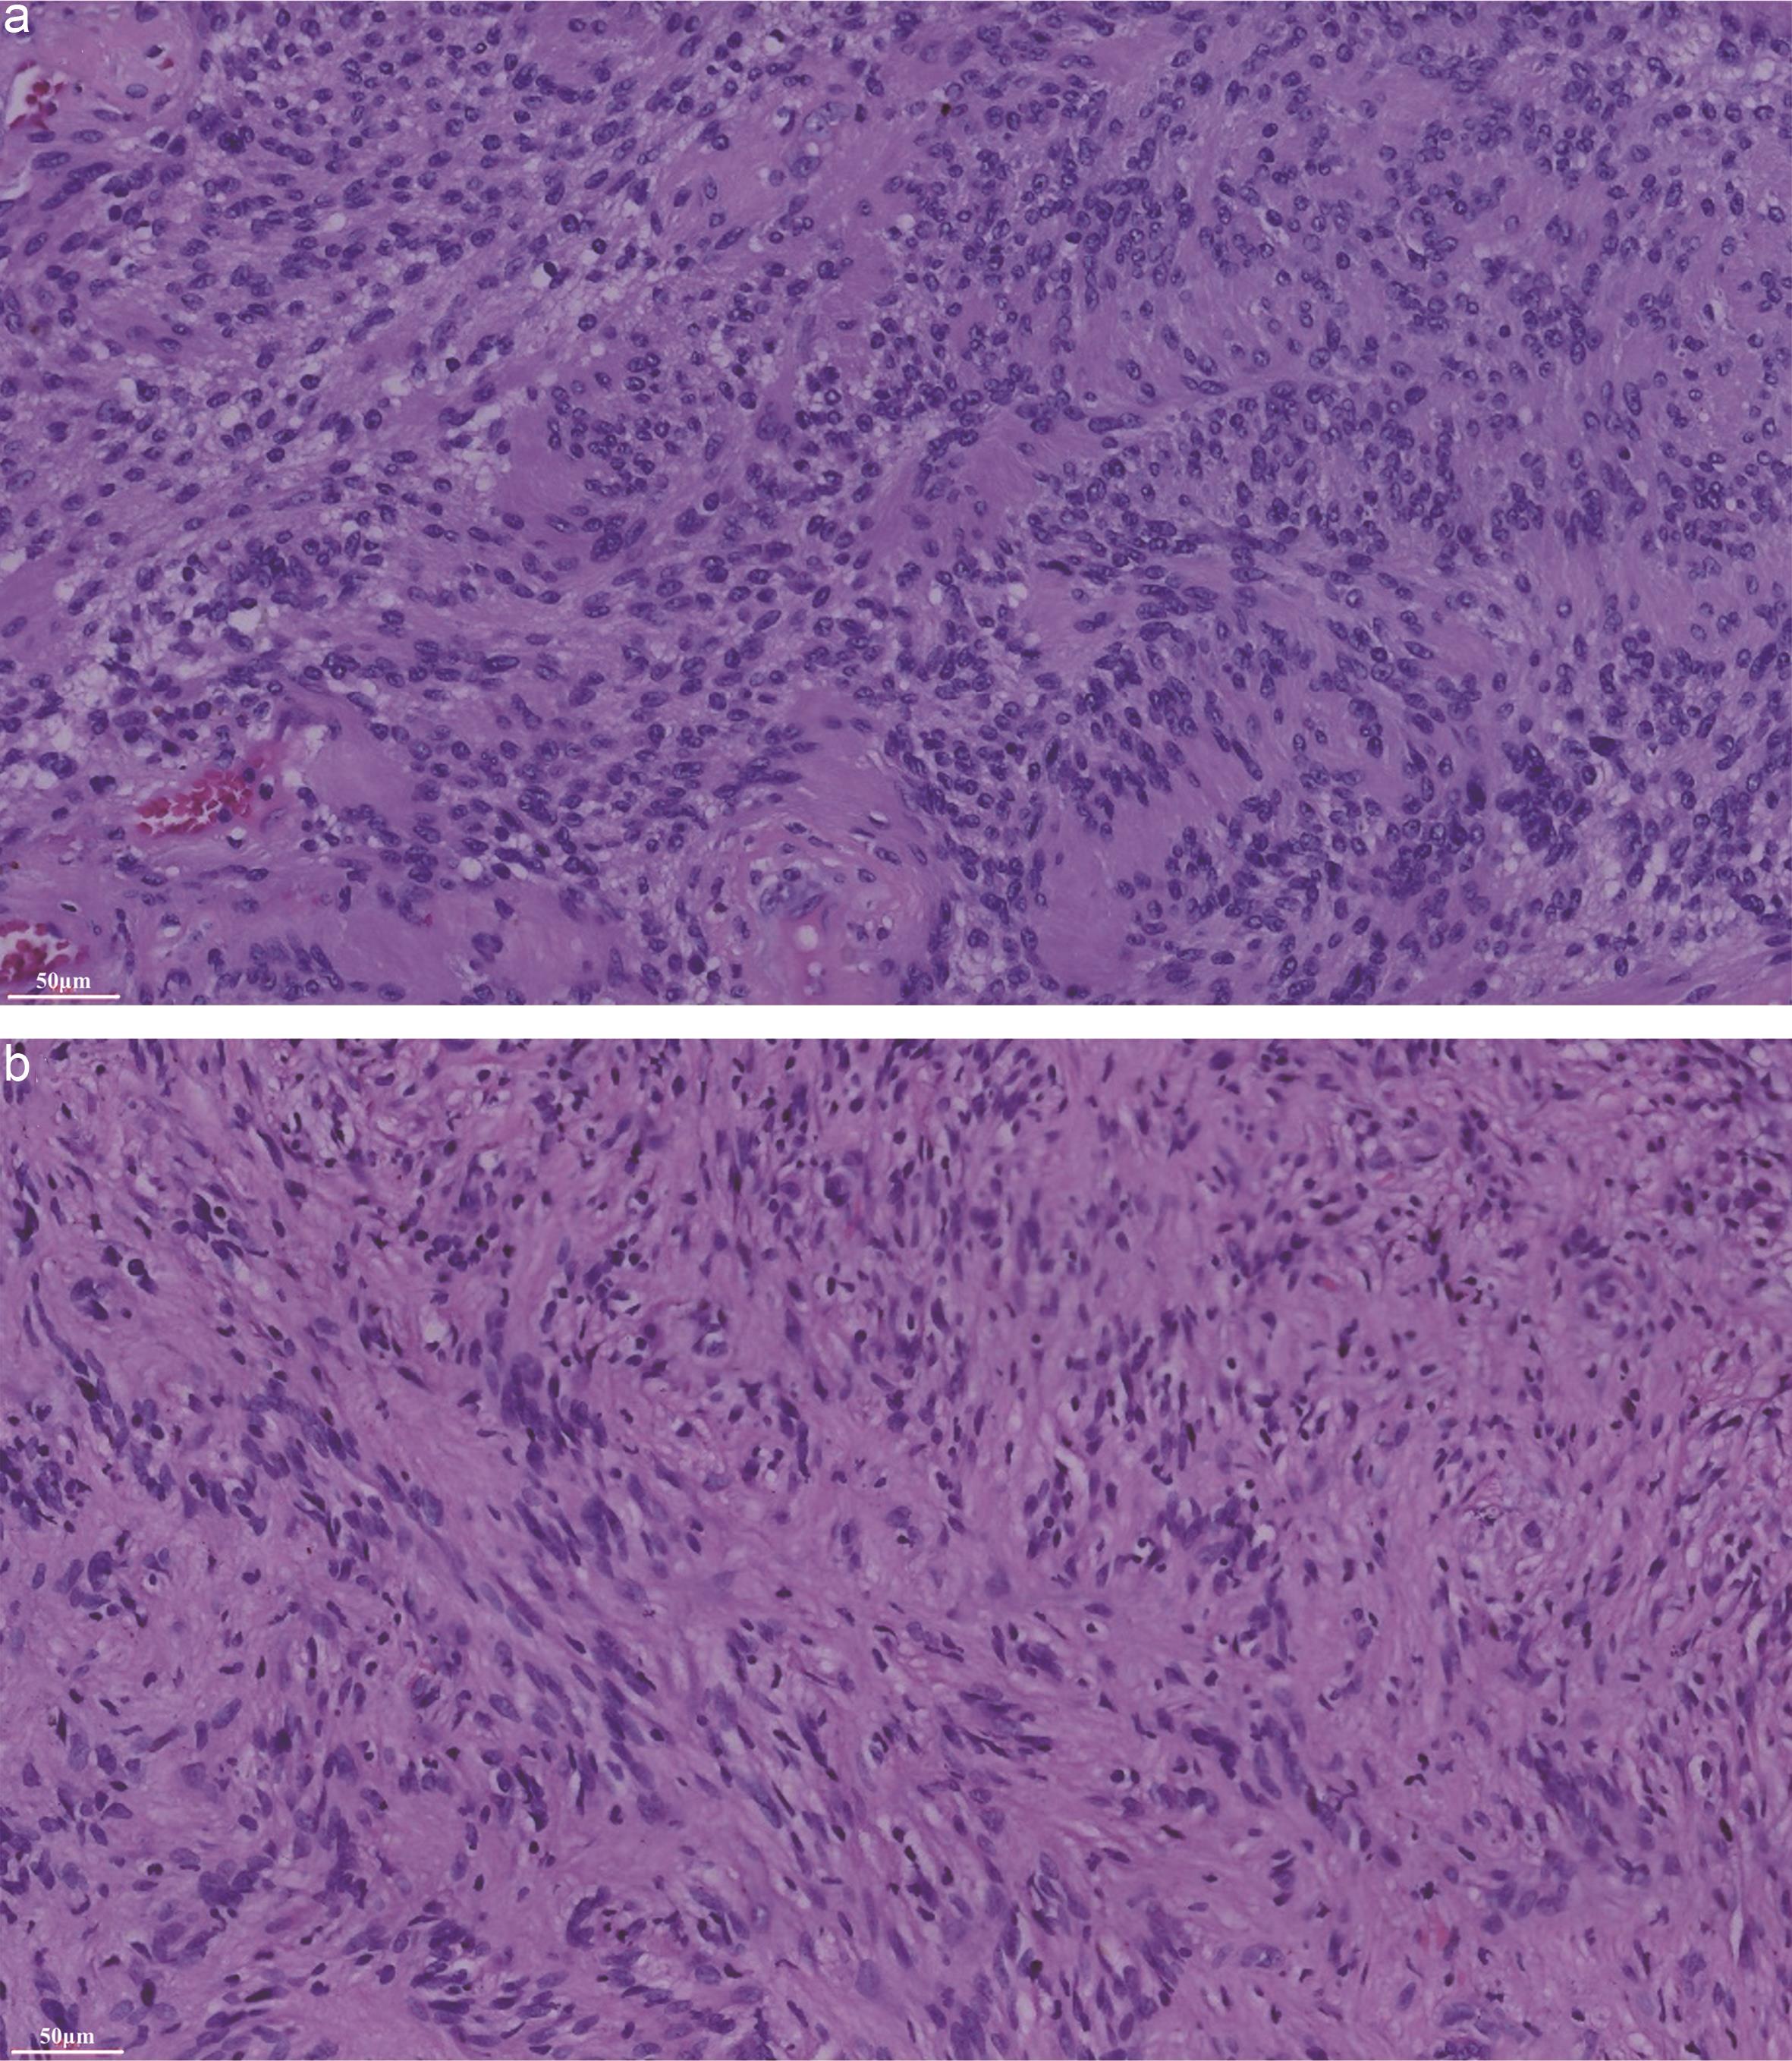

During the second-stage surgery (November 23, 2018), an anterolateral cervical approach was used for C4 vertebrectomy. A transverse neck incision was made, and careful dissection was carried out to expose the C4 vertebral body. Complete corpectomy of C4 was performed. A titanium mesh cage filled with autologous bone graft was inserted between the C3 and C5 vertebral bodies, and an anterior cervical plate was placed for stabilization. Both intraoperative and final histopathological evaluations of the tumor tissue confirmed the diagnosis of schwannoma (Fig. 2). Further immunohistochemical analysis revealed the tumor was positive for S-100, vimentin, and B-cell lymphoma 2, but negative for cluster of differentiation 34, smooth muscle actin and desmin. The Ki-67 labeling index was low, indicating limited proliferative activity.

The tumor tissue was removed (a) during the first operation and (b) during the second operation.

Fig. 2  The tumor tissue was removed (a) during the first operation and (b) during the second operation.

Histopathological images demonstrate the proliferation of spindle-shaped cells (a and b), which are compatible with a schwannoma.